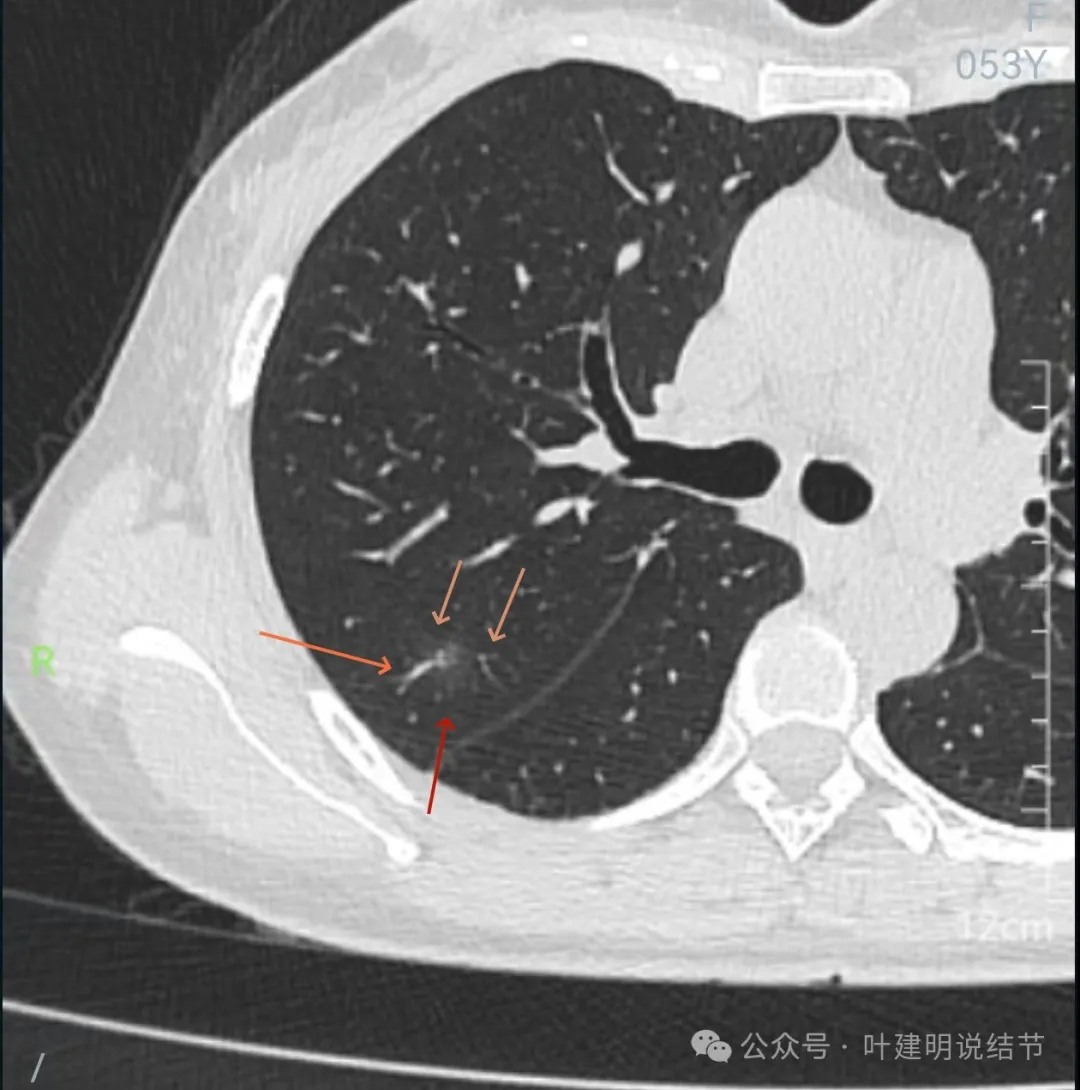

先来看2024年10月16日的影像:

右上后段混合密度结节,瘤肺边界欠清,有明显实性成分,边缘不光滑。

右肺很淡的磨玻璃阴影,伴进入的血管异常增粗,整体轮廓尚显清楚。

右下叶背段边界欠清的磨玻璃影,有血管刚好位于病灶处。

左下小片状模糊影,轮廓与边界欠清。

病灶出现,轮廓不清,瘤肺边界模糊,有血管穿行,血管有异常增粗。

血管壁有异常密度增高,病灶混合密度,轮廓总体在此层较清,但瘤肺边界不清。

病灶偏实性部分不密实,磨玻璃部分过淡且模糊。

边缘有毛刺,但不够锐利;外周磨玻璃成分密度过淡且界限不清;实性部分也显得不致密;与叶间裂距离近但没有任何牵拉影响。